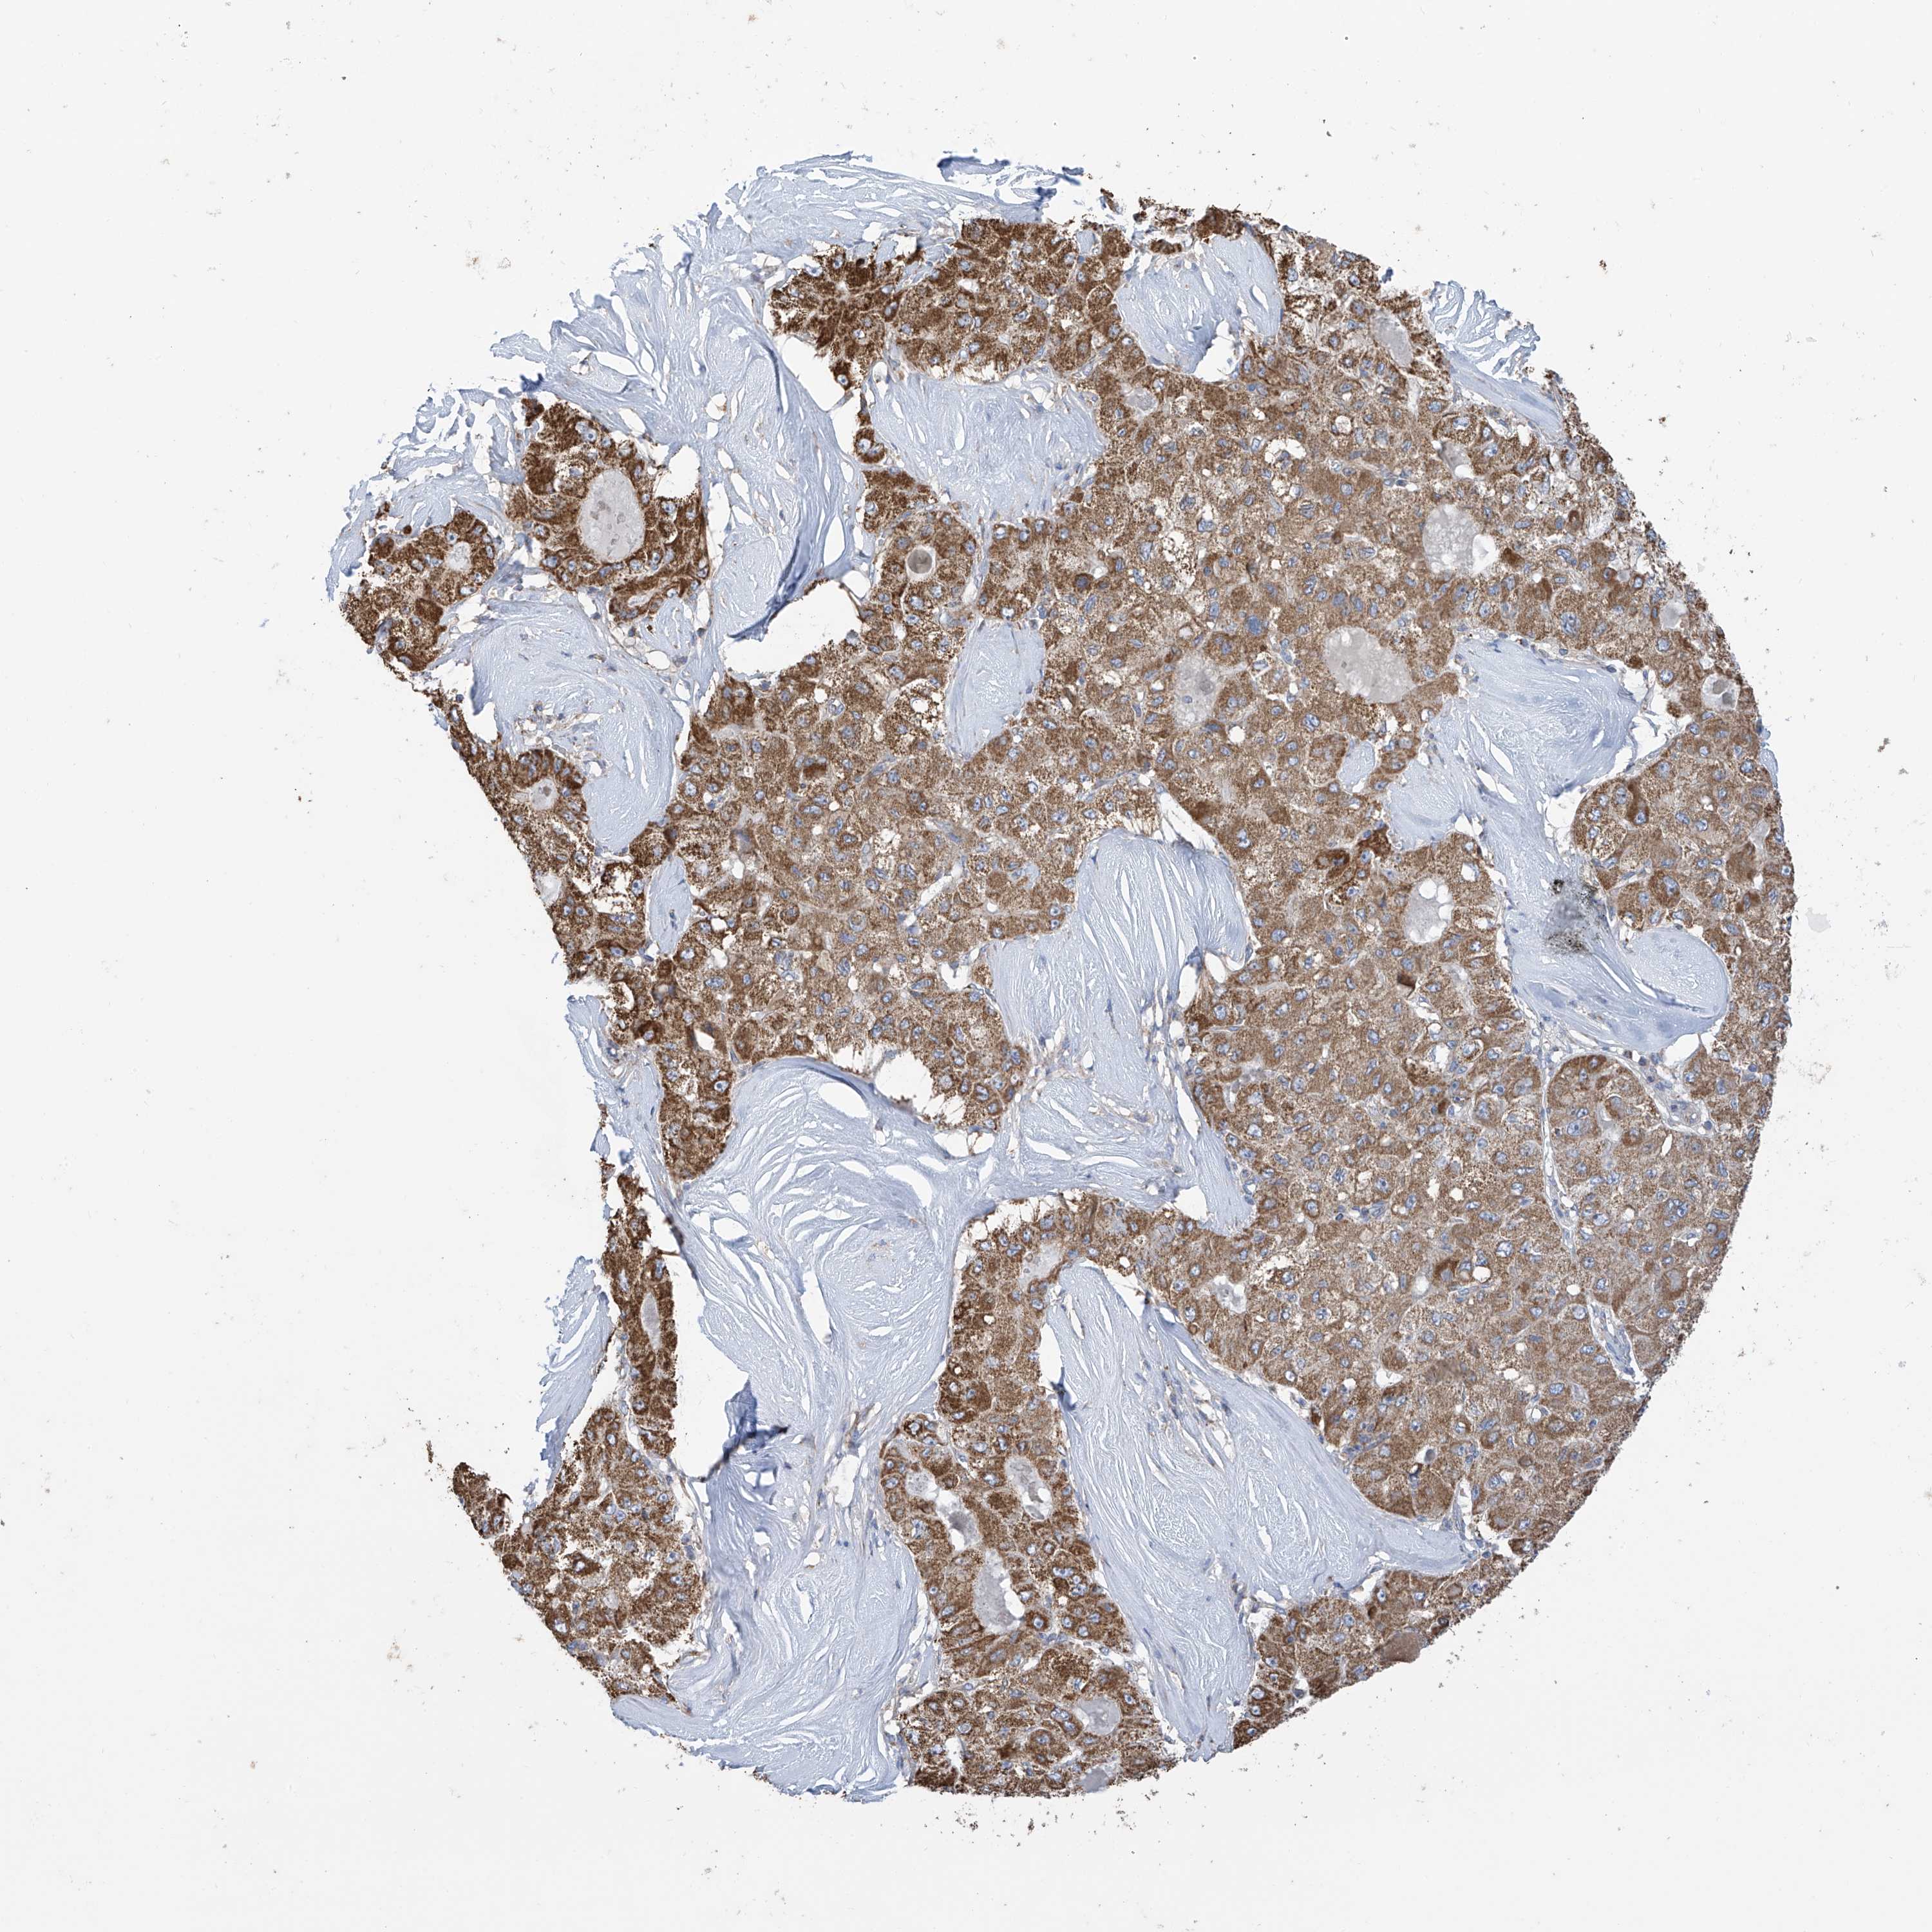

LIVER CANCER - Protein expressioni

A mouse-over function shows sample information and annotation data. Click on an image to view it in a full screen mode. Samples can be filtered based on level of antibody staining by selecting one or several of the following categories: high, medium, low and not detected. The assay and annotation is described here.

Note that samples used for immunohistochemistry by the Human Protein Atlas do not correspond to samples in the TCGA dataset.

Antibody stainingi

Antibody staining in the annotated cell types in the current human tissue is reported as not detected, low, medium, or high, based on conventional immunohistochemistry profiling in selected tissues. This score is based on the combination of the staining intensity and fraction of stained cells.

Each image is clickable and will lead to virtual microscopy that enables deeper exploration of all samples and also displays staining intensity scores, fraction scores and subcellular localization as well as patient and tissue information for each sample.

Antibody HPA034602

Antibody HPA034603

Antibody CAB033424

Staining

High

Medium

Low

Not detected

Intensity

Strong

Moderate

Weak

Negative

Quantity

>75%

75%-25%

<25%

None

Location

Nuclear

Cytoplasmic/membranous

Cytoplasmic/membranous,nuclear

Cholangiocarcinoma

Carcinoma, Hepatocellular, NOS